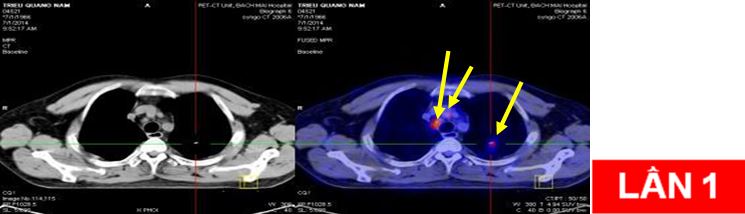

CHỤP PET/CT TOÀN THÂN

Hình ảnh khối u rốn u rốn phổi trái KT 4x4,5cm tăng hấp thu FDG mạnh, SUV=12,3.

Di căn hạch trung thất và hạch rốn phổi hai bên kích thước lớn nhất 2,5x3,6cm, SUV=6,8.

Di căn hạch trung thất tăng hấp thu FDG, nốt mờ thùy trên phổi trái tăng hấp thu FDG